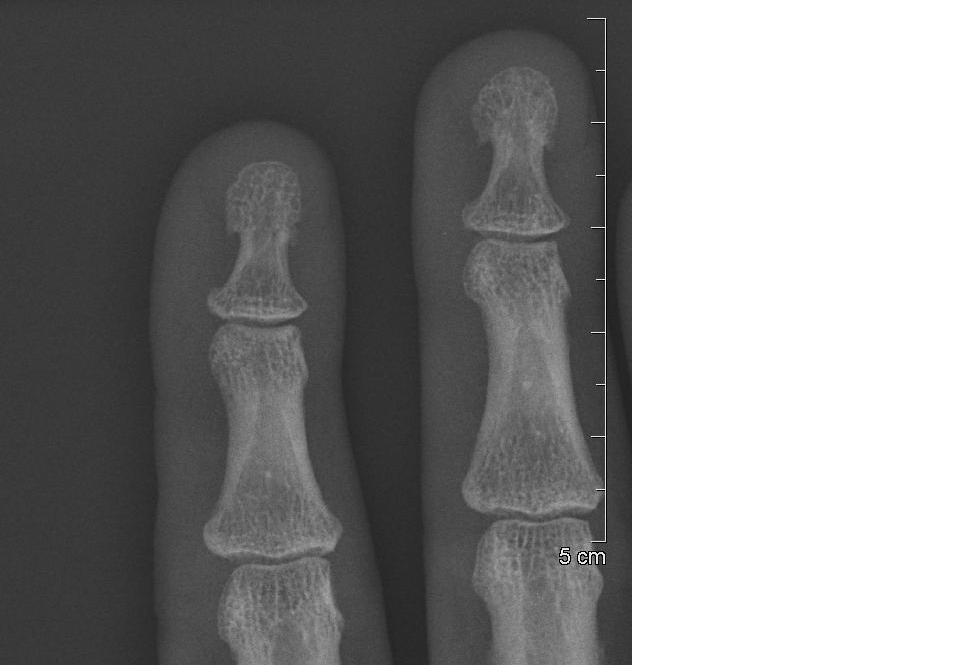

SOMEONE NAILED MY FINGER Fingernail X Ray The hand comprises the metacarpal and phalangeal bones. Fractures and dislocations are usually straightforward to identify, so long as the potentially injured bone is fully visible in 2 planes. The series examines in detail the distal, middle and proximal phalanx as well as. The finger series is comprised, conventionally of a posteroanterior, oblique and a lateral view. Fingernail X Ray.

SOMEONE NAILED MY FINGER